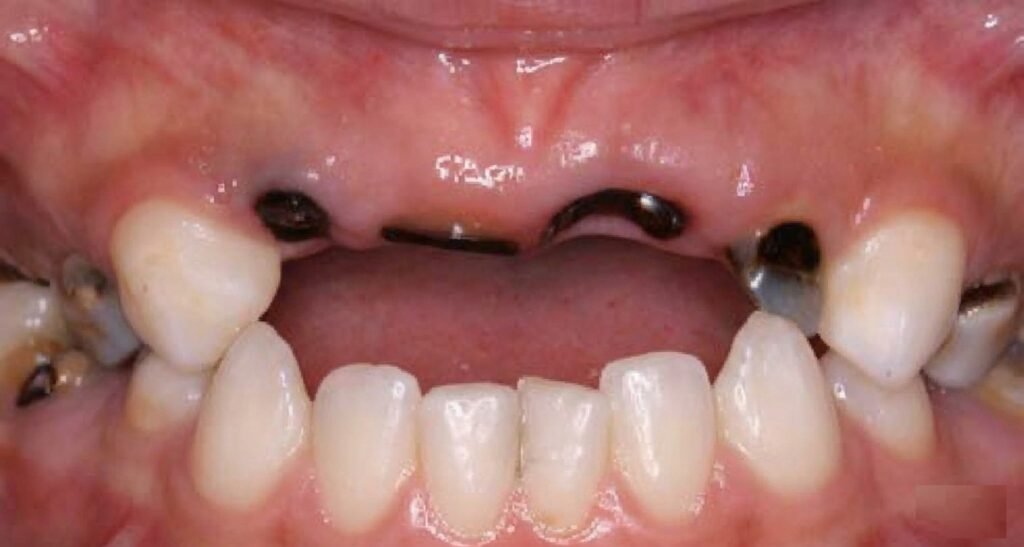

Carie du biberon ou syndrome du biberon

Ce type de pathologie s’observe en général chez l’enfant de plus de 12 mois. Sous ce terme, on décrit des caries rampantes dont l’étiologie est complexe. Ces caries sont dues à :

Cette pathologie se caractérise par une atteinte tout d’abord des faces vestibulaires et palatines des incisives supérieures, entraînant une destruction très rapide de la couronne et s’accompagnant d’une mise à nu, le plus souvent indolore, de la dentine. Les autres dents sont également touchées selon le même processus. Ce processus se produit en trois étapes :

Quatre stades cliniques peuvent être décrits :

Stade 4 : Atteinte traumatique

- Diagnostiqué à l’âge de 30-48 mois.

- Caractérisé par une fracture de la couronne des dents antérieures maxillaires par suite de la destruction amélo-dentinaire.

- Ces dents sont nécrosées dans la plupart des cas.